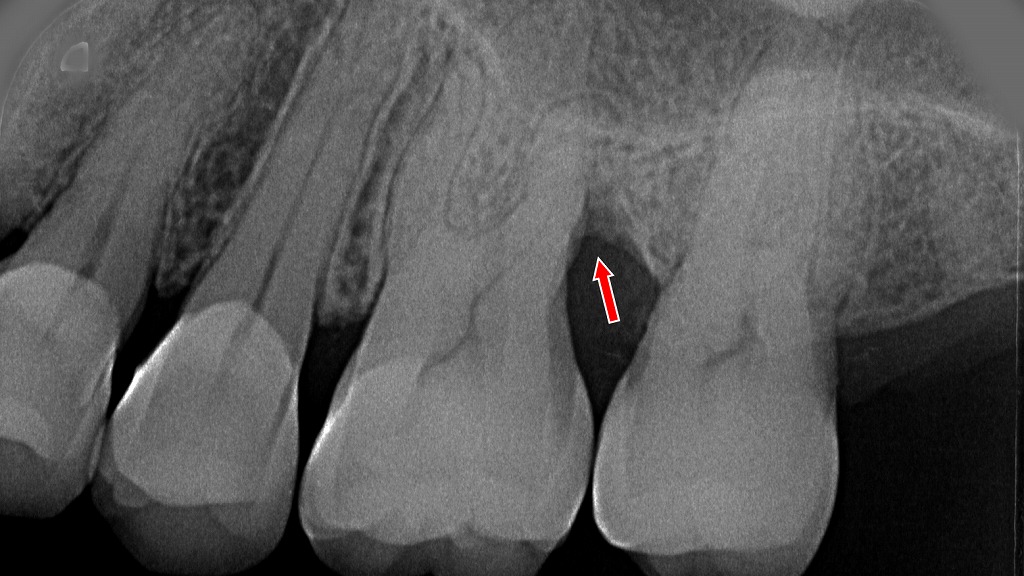

デンタルX線診断

写真は、上顎2番(側切歯)の歯肉にフィステル(膿が出る場所)が形成されたので、問題の部位を特定する為に、フィステルからガッタパーチーポイントを入れてデンタルレントゲンを撮影したものです。

フィステル形成の原因が根尖病巣か歯周病かの鑑別は、ガッタパーチーポイントの先端が赤丸で示されたところで止まっている為、歯周病が原因と特定されます。

レントゲン写真で確認したように、上顎2番の近心側に深い垂直性の歯周ポケットが存在している事が分ります。